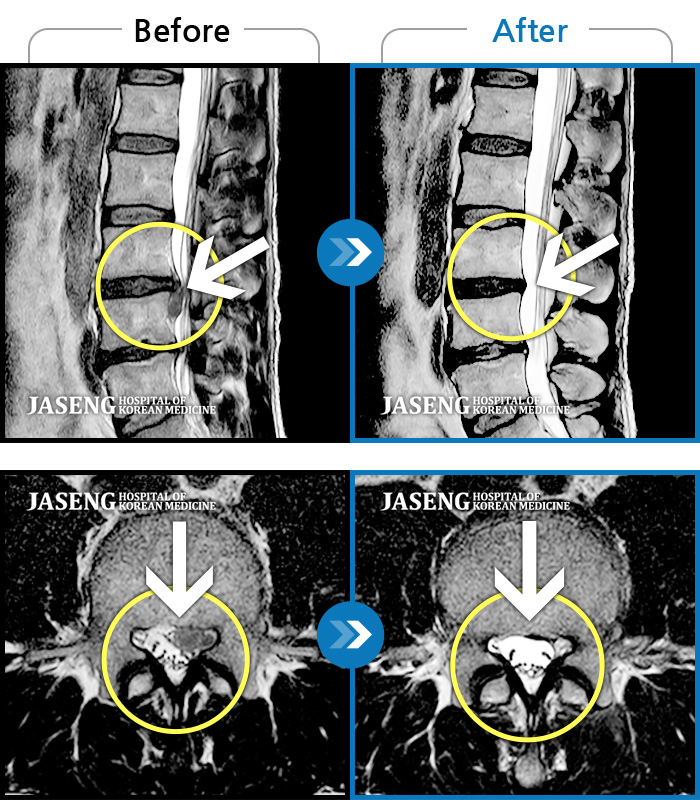

Before

After

환자에게 사전 동의를 받아 동일 조건에서 촬영되었습니다.

개인에 따라 치료 후 부작용이 발생할 수 있으니 의료진과 상담 후 치료를 진행하시기 바랍니다.

허리와 좌측 다리 통증이 심하고 발목 힘이 빠져요.